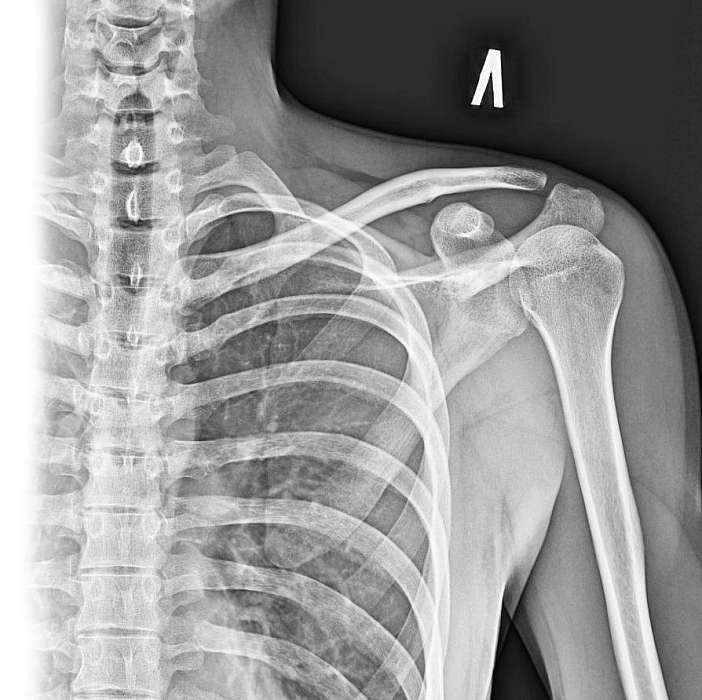

Рентгенография лопатки – важный метод прицельного исследования, который позволяет оценить состояние лопатки.

Диагностическая услуга выполняется в двух проекциях.

Рентген позволяет оценить наличие костно-травматической патологии лопатки.